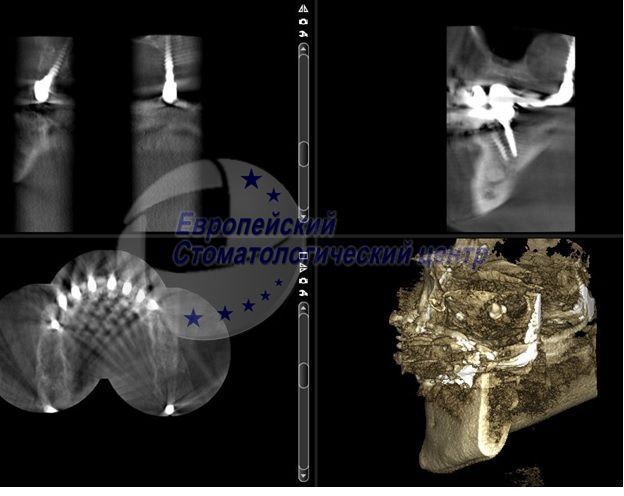

КТ через рік після операції протезування металокерамічними коронками